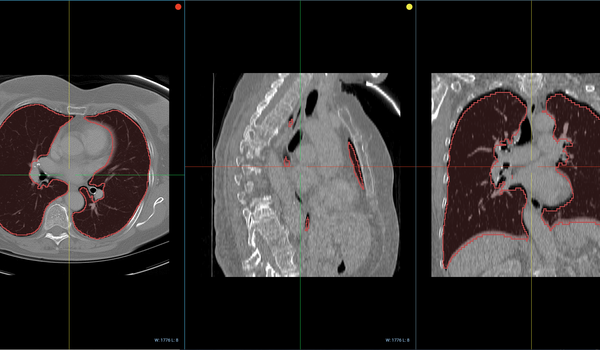

Through its integration with Jupyter, Sonador provides an ideal environment for rapid prototyping AI models and preparing 2D and 3D medical imaging data. Data can be retrieved from Orthanc using the Python client library, converted to NumPy arrays using PyDICOM, analyzed using SimpleITK, and visualized with ITK Widgets.